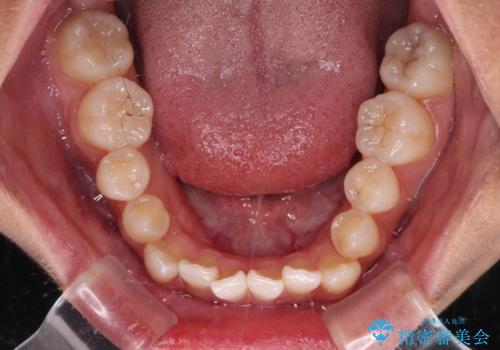

- 前歯の開咬と、上顎前歯の八重歯やデコボコを気にして来院された患者様です。

上顎歯列が狭窄していたため、急速拡大装置により上顎骨を側方に拡大し、その後ワイヤー装置にて矯正治療を行うこととしました。

急速拡大装置で上顎骨を十分に拡大できたことで、非抜歯で八重歯を歯列に納めることができました。